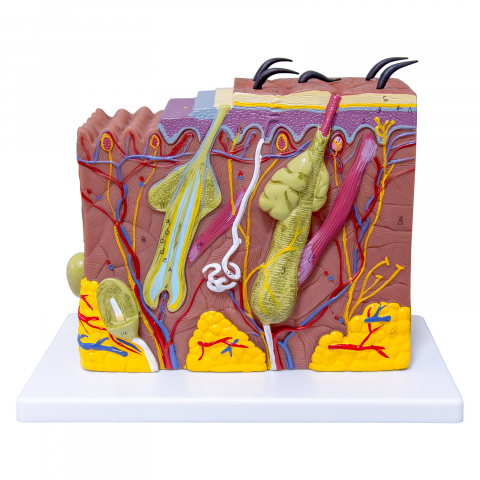

Modelul este conceput din material plastic PVC și este frumos colorat.

Acest model este conceput ca ajutor vizual pentru predarea cursurilor de anatomie umană și igienă. Este folosit pentru a demonstra structura dintelui, la studiul sistemului digestiv în gimnaziu, liceu și școli postliceale medicale.

Acest model are înălțimea de 23-26 cm, prezintă 3 rădăcini, o secțiune longitudinală prin care se poate observa structura interioara a dintelui, este conceput din material plastic PVC și este frumos colorat.